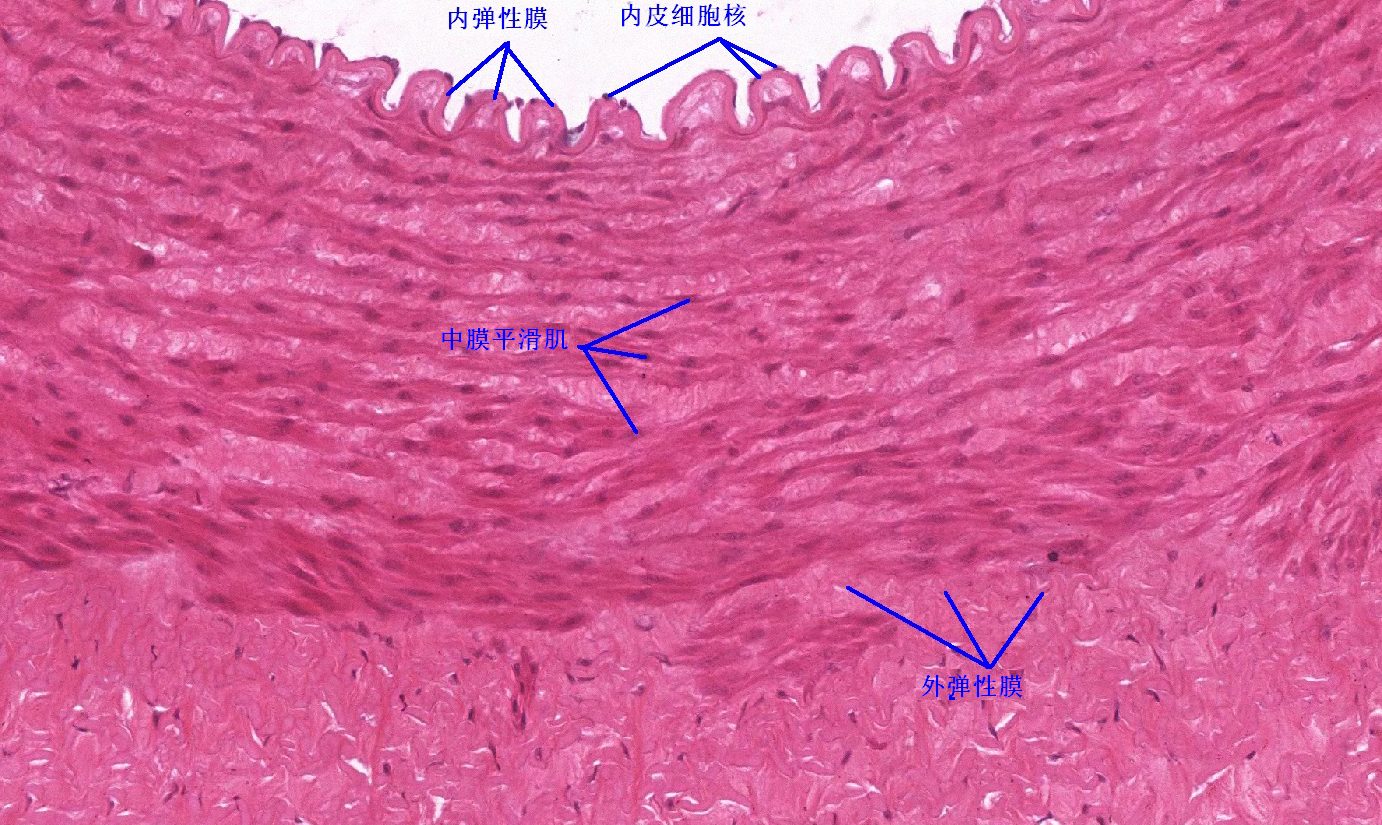

6 第六单元 循环系统

6.1 循环系统切片库

6.2 循环系统微课

6.3 循环系统课件